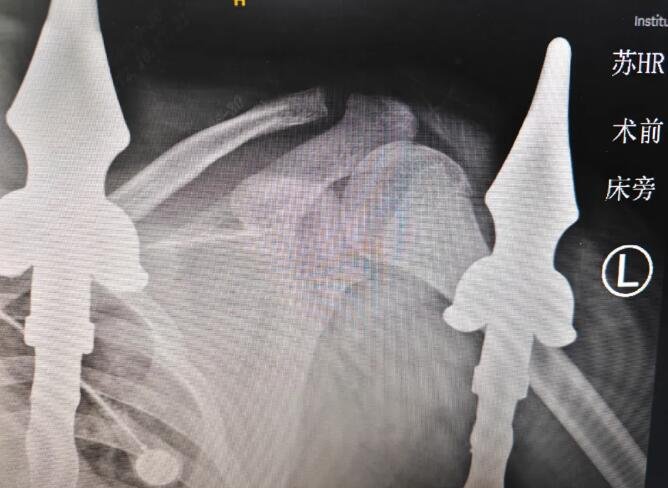

伤处X射线图片

少年受伤部位为左上臂,肩、腋部位血管、神经密集,如果受到不可挽回的伤害,很可能造成一辈子的行动障碍,可谓“凶险无比”。铁栅栏刺穿的路径与主要血管、神经“擦身而过”,最近处仅差1厘米左右,又及时得到了高水平医疗团队的处理,又可谓“有惊无险”。

为了保持孩子的身体功能,需要将破损的血管和神经重新连接。遇到这种病例,就到了“显微外科手术”登场的时候。医生们小心翼翼地避开重要血管、肌肉、神经,慢慢取出异物,并对伤处进行清创。

“通过显微外科技术,我们实施了左上肢清创血管神经肌肉撕脱皮肤修复异物取出术,对周围神经和血管进行吻合,并缝合肌肉与皮肤。手术效果良好,从目前来看,预计对以后的肢体功能影响不大。”李甲医生介绍。“后续通过我们的全程照护服务,一方面妥善护理患者,另一方面也为家长减轻陪护的负担,能够更好促进患者从生理、心理多方面康复。孩子以后可以恢复正常的学习生活,包括上体育课也问题不大。”